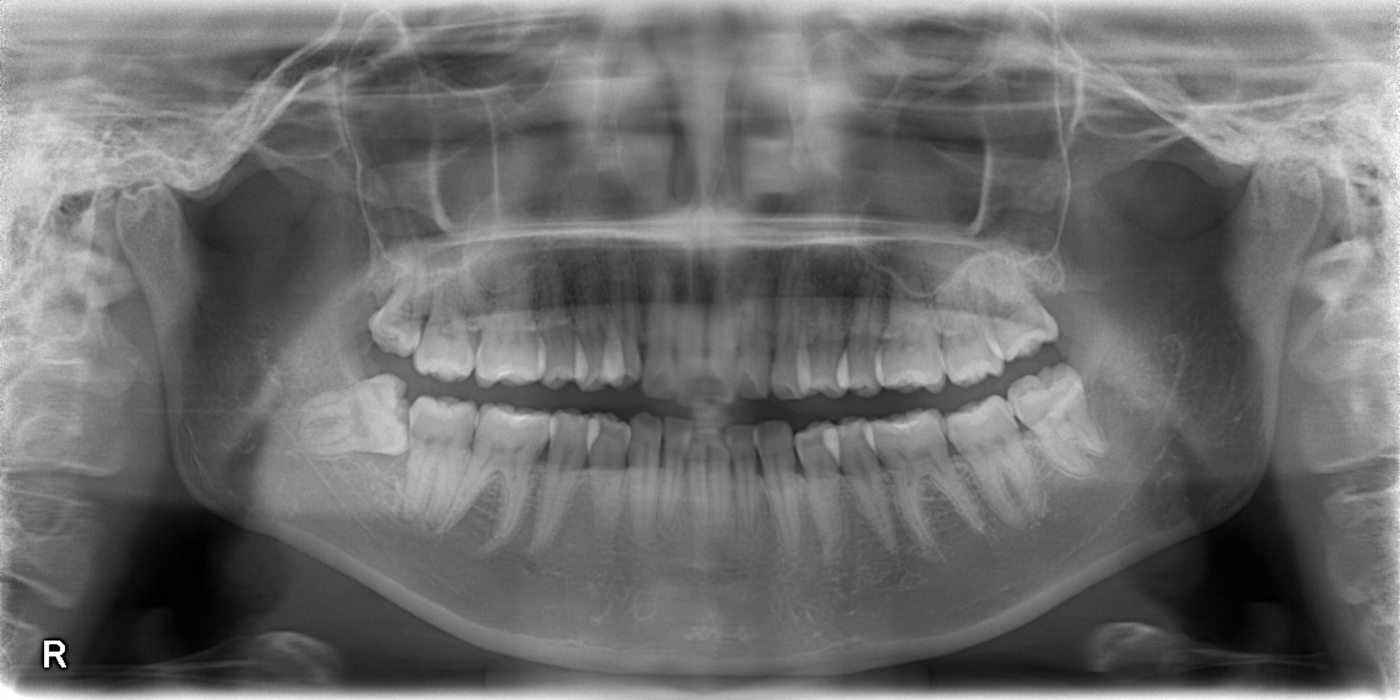

親知らずの抜歯は外来通院をしながら1本ずつ抜歯していく方法と、複数の親知らず(上下左右で4本)を入院下に一回で抜歯する方法とがあります。. 不利な点としては、入院費(当科では2泊3日体制が主ですので、外来での順次抜歯に比べて約1万3000円.. みなさんは親知らずを抜歯するのに手術が必要な場合があることを知っていますか?. よって埋伏している親知らずを4本一泊二日の入院で全身麻酔下で抜いた場合の金額は3,500×4+20,000+30,000=64,000円ぐらいで、その他の処置料や検査料が加わります。.